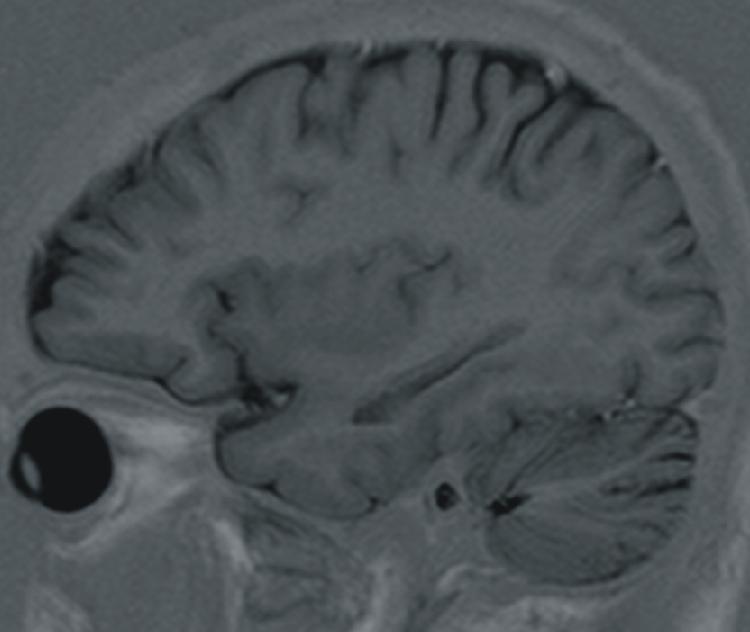

| Sulcus centralis |

| Insula |

| Claustrum |

| Corpus amygdaloideum |

| Putamen |

| Hippocampus |

| Ventriculus lateralis - cornu temporale |

| Ventriculus lateralis - cornu occipitale |

| Ventriculus lateralis - plexus choroideus |

| Cerebellum |

| Fissura prima |

| Fissura horizontalis |